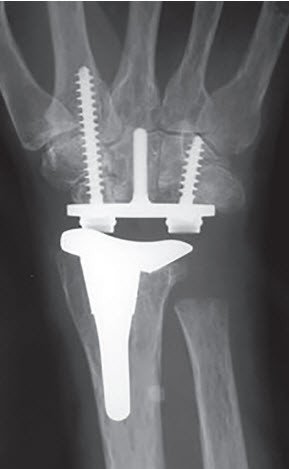

Zu den Hauptspezialitäten gehören der Kunstgelenkersatz an der Hand, komplexe Handgelenkchirurgie und die Behandlung des Morbus Dupuytren, wobei hier auch eine neue konservative Therapie mittels Kollagenase-Infiltration zum Einsatz kommt. Die Patienten der Handchirurgie profitieren von einer umfassenden fachspezifischen Betreuung, die auf langjähriger Erfahrung, kontinuierlicher Lehrtätigkeit und wissenschaftlicher Forschung basiert. Neben Erstbehandlungen werden auch detaillierte Zweitmeinungen und Gutachten angeboten.

Zu unseren operativen Spezialgebieten zählen insbesondere der Kunstgelenkersatz, Weichteileingriffe, Revisionsoperationen und Rückzugsoperationen sowie die Behandlung von Patienten mit rheumatoider Arthritis.

- Gelenkersatz an Hand- und Fingergelenken

- Rheumachirurgie von Hand und Handgelenk